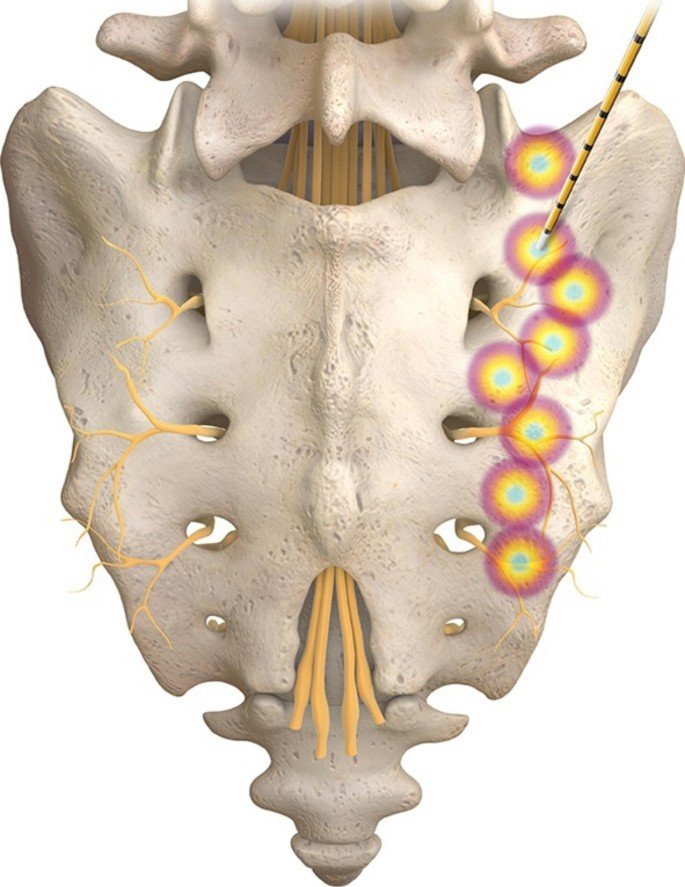

right sacroiliac joint target lesion sites. On the right side, L5 dorsal ramus, 2,4:30 and 6 o’clock for S1 and S2, while S3 only 2, 4:30 o’clock were targeted.Radiofrequency Ablation is a minimally invasive procedure that uses heat generated by radiofrequency waves to disrupt the nerves that transmit pain signals from the sacroiliac joint to the brain.

How RFA works

During the procedure, a specialized needle with a heating element at the tip is guided into the sacroiliac joint using fluoroscopy or ultrasound. The nerves responsible for transmitting pain signals are then heated and destroyed, providing long-lasting pain relief.